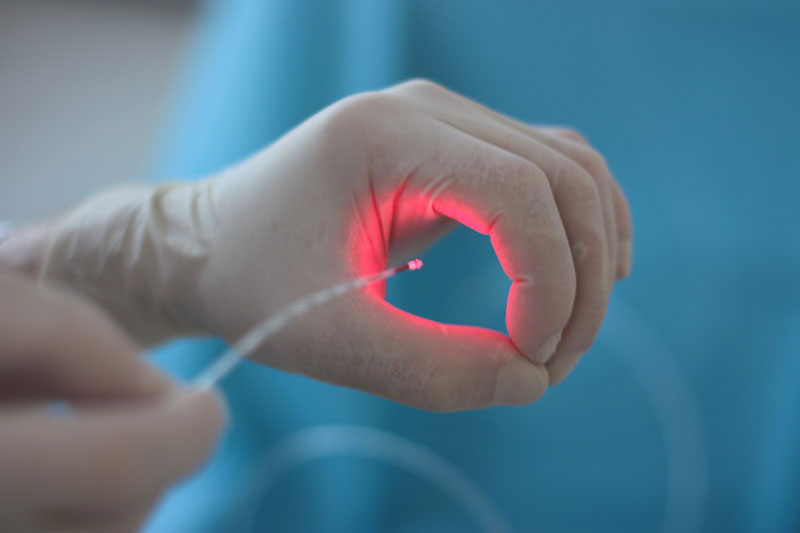

Пироговский Центр стал российским лидером в области эндоваскулярных методик лечения хронических заболеваний вен нижних конечностей

В Центре впервые внедрена неинвазивная технология дистанционной ультразвуковой абляции опухолей паренхиматозных органов HIFU

Проведены первые операции при миоме матки, опухолях печени, поджелудочной железы, надпочечников и др.